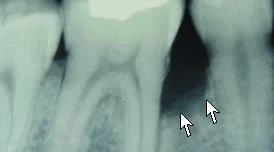

Before Regeneration

After Regeneration